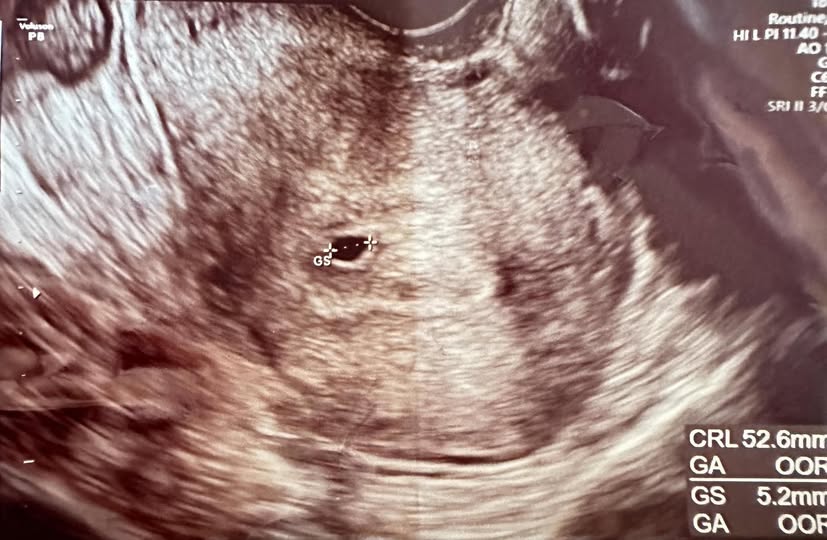

Hỏi – Chậm kinh 15 ngày nhưng siêu âm chỉ thấy túi thai nhỏ có sao không?

Mn ơi, tính theo ckkn thì nay e chậm kinh 15-16 ngày r, mà siêu âm chỉ có túi thai 5.2mm thôi, là bất thường tiên lượng rất xấu đúng không ạ

Siêu âm thôi chưa đủ cần khám + xét nghiệm betaHCG để theo dõi sự phát triển của thai, nên em cần kết hợp khám thai nữa nhé.

Siêu âm chỉ phản ánh một phần, em nên làm thêm xét nghiệm betaHCG và theo dõi để biết thai phát triển bình thường hay không nhé.